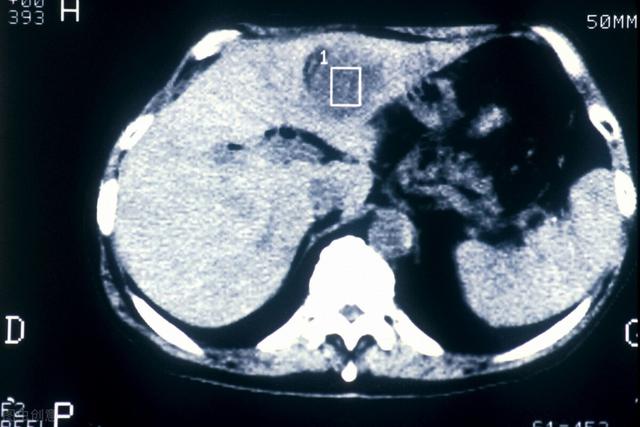

(Comme indiqué : cancer du foie métastatique)

- Si une échographie du foie ne révèle pas de tumeur dans le foie, ou si la nature de la tumeur ne peut être déterminée, une alpha-fœtoprotéine élevée est hautement suspecte de la présence possible d'un carcinome hépatocellulaire.Une tomodensitométrie du foie peut être réalisée.Je recommanderais d'emblée une tomodensitométrie améliorée du foie, car cette technique est relativement efficace pour identifier les tumeurs hépatiques.